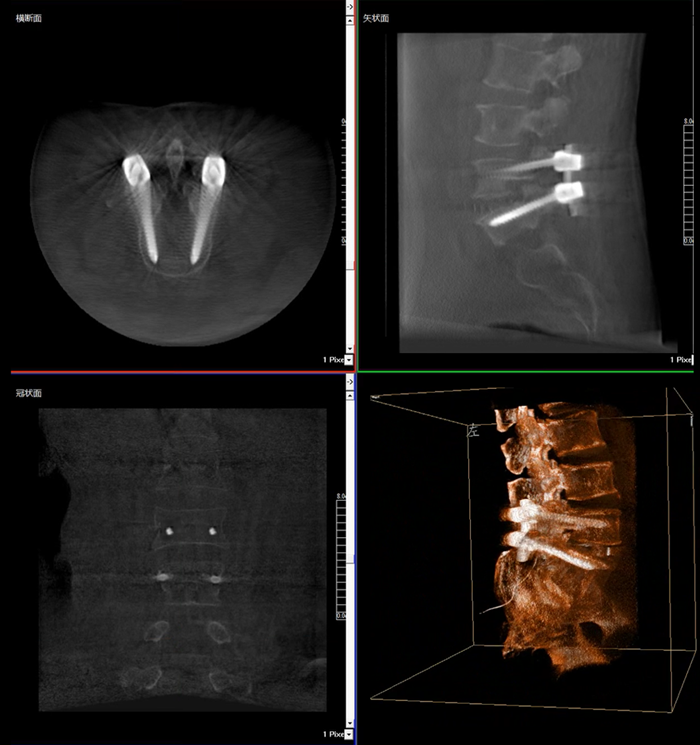

移動式三維C形臂,又稱骨科三維C臂,就是將傳統(tǒng)二維與“類CT模式”相結(jié)合的升級版C形臂,能在術(shù)中快速地生成橫斷面、矢狀面、冠狀面斷層圖像和三維立體圖像。通過不同方位的斷層圖像,能夠更清晰、完整地顯示椎體及其附件的解剖學(xué)結(jié)果,直觀地分析病變與周圍組織的立體空間關(guān)系,三維斷層成像能夠使手術(shù)模擬和手術(shù)方案的制定更加準(zhǔn)確。

在MPR圖像中,冠狀面、矢狀面和橫斷面的信息大大提高了醫(yī)生對于病灶區(qū)以及手術(shù)效果的判定。

術(shù)中實時三維影像帶來的更加豐富的信息,可以作為醫(yī)生手術(shù)執(zhí)行的判斷基礎(chǔ),以及手術(shù)操作后實時的影像判斷依據(jù),從而保障手術(shù)效果。

在既往的手術(shù)中可能會出現(xiàn)這樣的情況:術(shù)后在影像科CT檢查中發(fā)現(xiàn)某個手術(shù)效果需要調(diào)整,這時往往需要返臺、翻修等才能解決。而移動式三維C形臂提供的術(shù)中三維影像功能可以將這一步驟合并至手術(shù)流程中,有效地降低醫(yī)患雙方的風(fēng)險,為手術(shù)保駕護(hù)航。